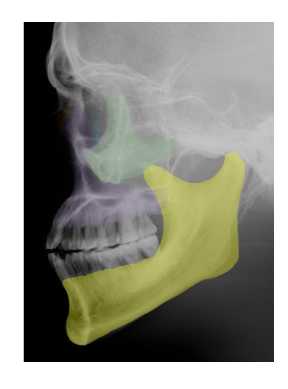

Cranial and Facial Bones

Students will use images and descriptions to reinforce their knowledge of the cranial and facial bones.

| MANDIBLE |

in yellow,  | ETHMOID |